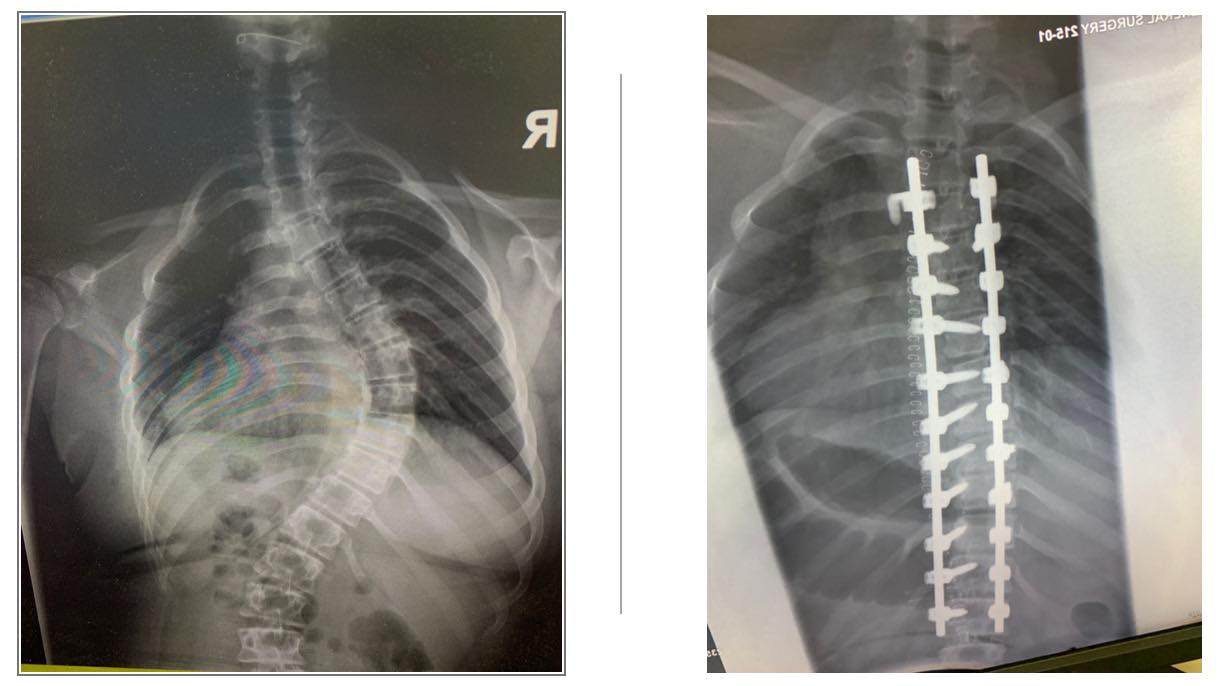

و تُظهر الصور قبل العملية مدى انحناء العمود الفقري، في حين تُبرز الصور بعد العملية التحولات الكبيرة التي تم تحقيقها. هذه التحولات لم تُحسن فقط صحتها الجسدية، بل رفعت من ثقتها بنفسها و جودة حياتها بشكل عام.